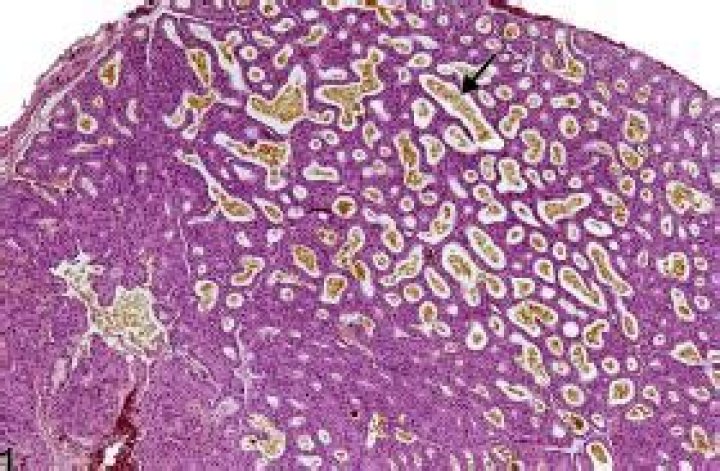

The Harderian gland is a gland found within the eye's orbit that occurs in tetrapods that possess a nictitating membrane. The gland can be compound tubular or compound tubuloalveolar, and the fluid it secretes varies between different groups of animals.

Harderian glands are pigmented lacrimal glands located posterior to the ocular globes. These secretory glands release a lipid- and porphyrin-rich material that lubricates the eyes and eyelids.

Do mice secrete porphyrin?

Comment: Lipids are the primary secretory products of the rodent Harderian gland, but porphyrin pigment is also synthesized and secreted. ... Incidentally occurring porphyrin deposits are generally more prominent in the Harderian glands of female rats and mice.